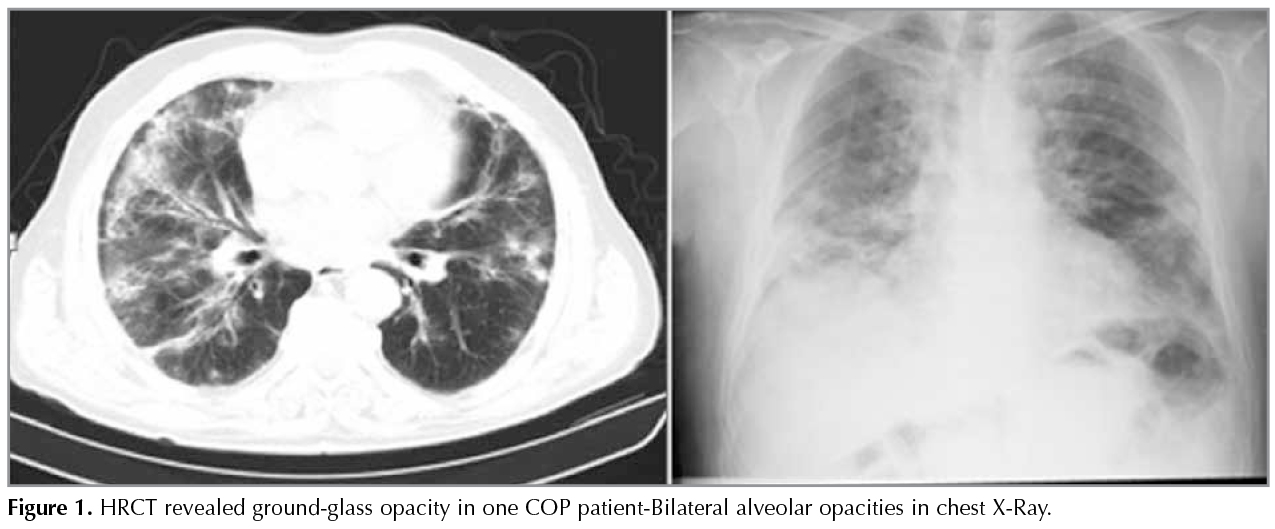

In HRCT scans; 69 (41.8%) patients had the typical multiple patchy bilateral opacities, 76 (46%) had focal lesions (solid mass, cavitating mass) and 6 (3.6%) had infiltrative opacities (Figure 1, 2, 3). Other features of OP including multiple nodules (12 patients, 7.2%), band- like opacities (1 patient, 0.6%), reversed halo sign (1 patient, 0.6%) were also reportedon HRCT scans (Figure 4). Pleurisy was seen in 14 patients. Evaluation of COP and secondary OP patients according to their radiological patterns were givenin Table 5. Eighty-nine (53.9%) patients were diagnosed by TTFNB, 52 (31.5%) by open lung biopsy (lobectomy, wedge resection, segmentectomy) and 24 (14.5%) by TBB. Diagnostic methods according to the radiological appearance were given in Table 6.

Figure 1